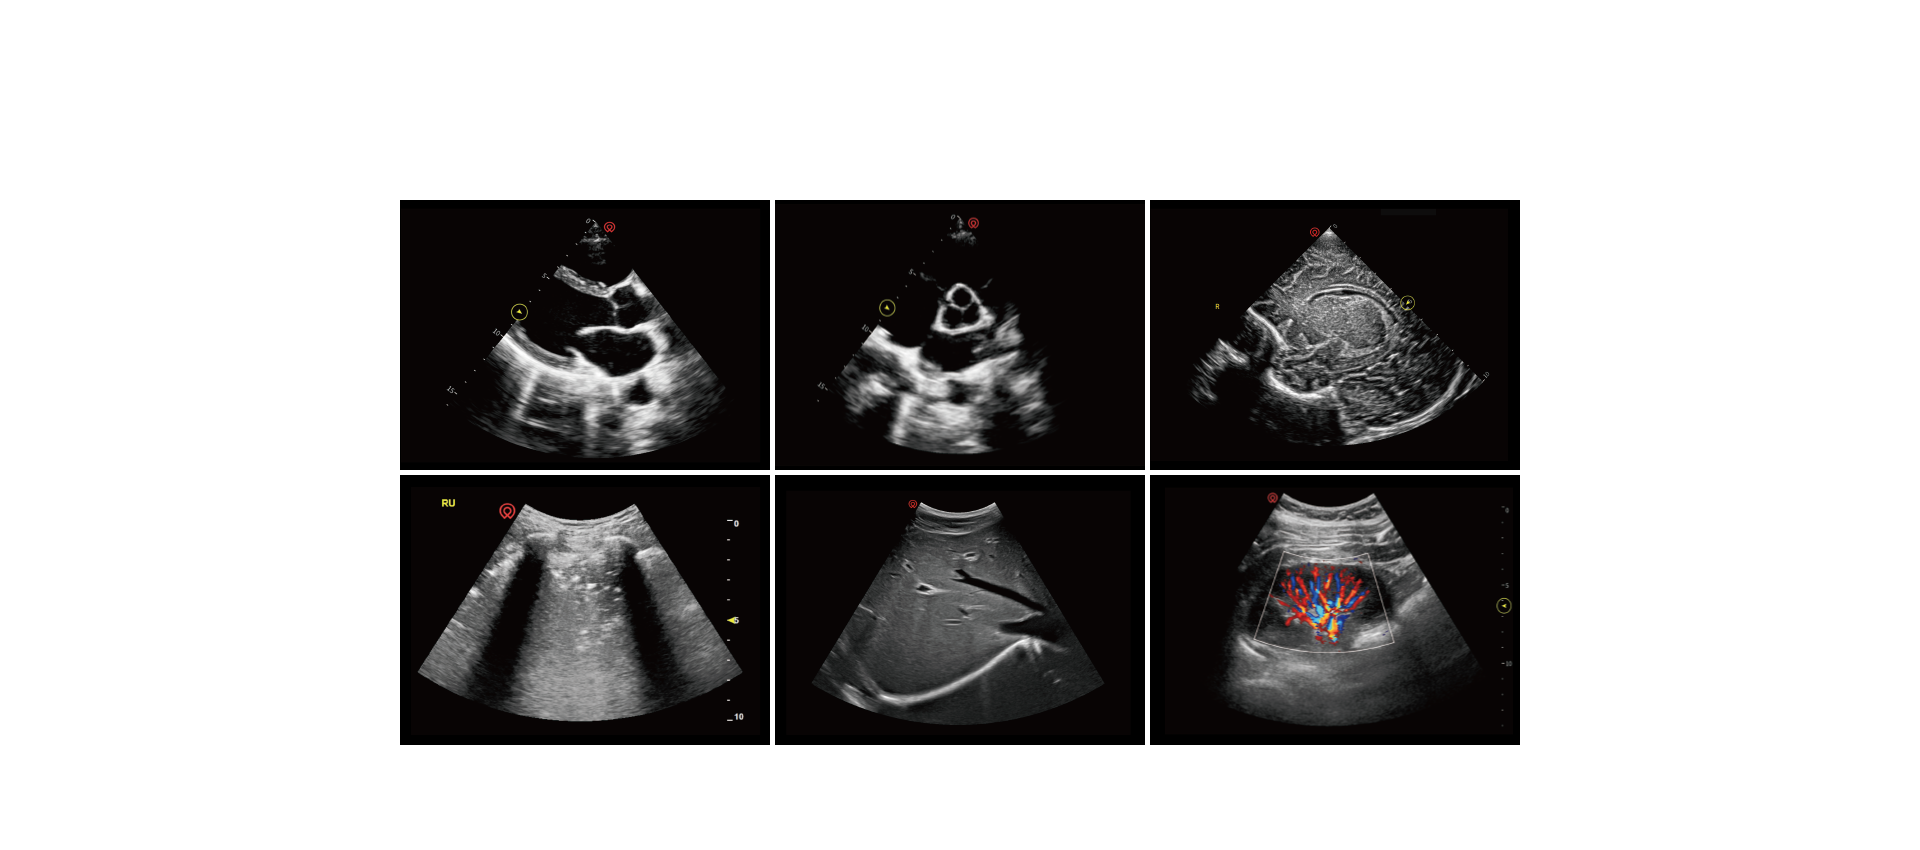

exceptional image quality

application pictures

comprehensive probe selection

a versatile range of transducers designed to support cardiac, lung, abdominal, vascular, and musculoskeletal imaging

• optimized for adults, pediatrics and neonates

• tailored to meet multi-site diagnostic needs in emergency care

• enabling fast, accurate evaluations when every second counts